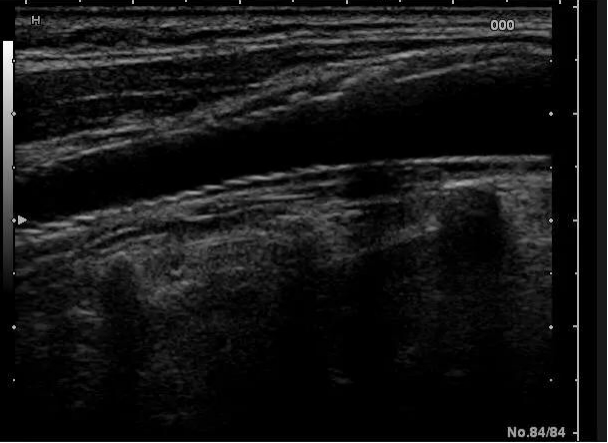

来,先让我们的头颈联合超声看看血管里的小霸王长啥样?

如果斑块太硬了(强回声钙化的斑块),支架容易撑不开啊!

如果斑块不完整,缺了个口张了个嘴(溃疡斑块或极低回声斑块伴出血),支架后它还不服,会吐东西把支架堵住(血栓形成)!

斑块完整没有破,回声均匀,才能考虑放支架。